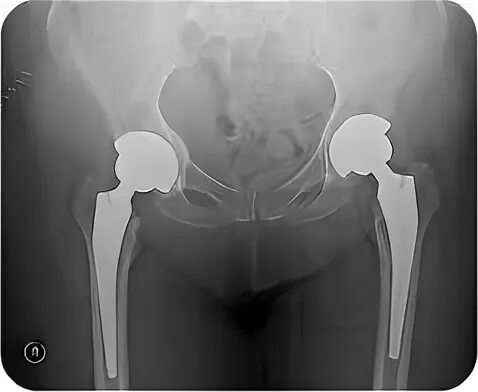

Эндопротезирование тазобедренного сустава после 3 месяцев